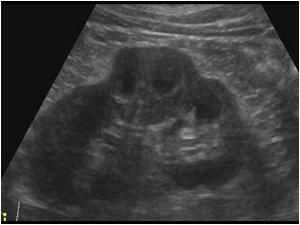

3-Duplex kidney

هذا مصطلح واسع يشمل عدة متغيرات منها وجود كليتين ملتصقات ببعض أو وجود two collecting systems في كلية واحدة. وهذه أيضا يوجد بها متغيرات أخرى من ناحية وجود حالب واحد أو حالبين ووجود شريان واحد أو اثنين.

يوجد هذا المتغير في قرابة ١٠٪ من الناس الطبيعيين. ويجب على الأخصائي التأكد من عدم توسع الحالبين وأيضا عدم وجود انسداد في أحد collecting systems وتحديدا العلوي.